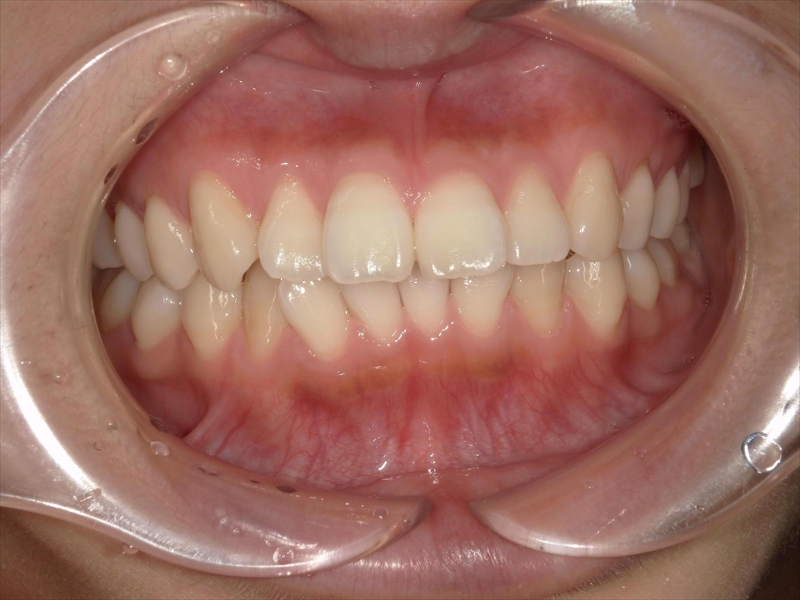

この患者様は、重度の出っ歯があり、下顎前歯には叢生が認められました。

また、奥歯の噛み合わせにも問題があり、本来は半歯分ずつずれて噛み合うべきところが、正しく機能していない状態でした。

患者様は、「出っ歯で口が閉じられず、写真が嫌だった。」「笑う際も気になって思いっきり笑えない。」と悩まれておりました。

治療前後 写真